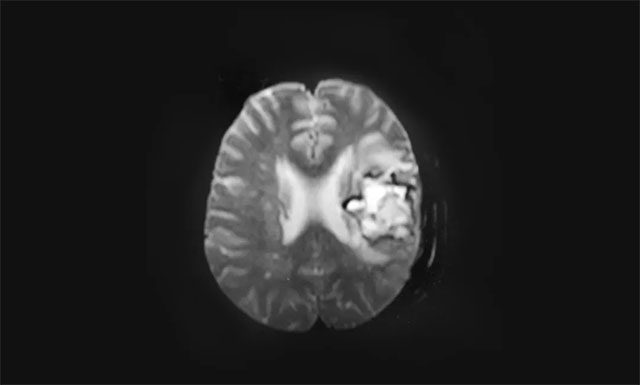

39的小徐(化名)既往有高血压、冠心病多年,血压最高达收缩压180mmHg,舒张压100mmHg。正值壮年的他从事财务工作,他是家中的顶梁柱,家有爱妻和两个孩子,一家...[详情]

“我、相信、会更好!”“我相信会更好!”“很好,来我们再说一遍!”在上海蓝十字脑科医院神经内科4A病区副主任医师殷昌凤的引导下,脑出血术后一直失语偏瘫的...[详情]